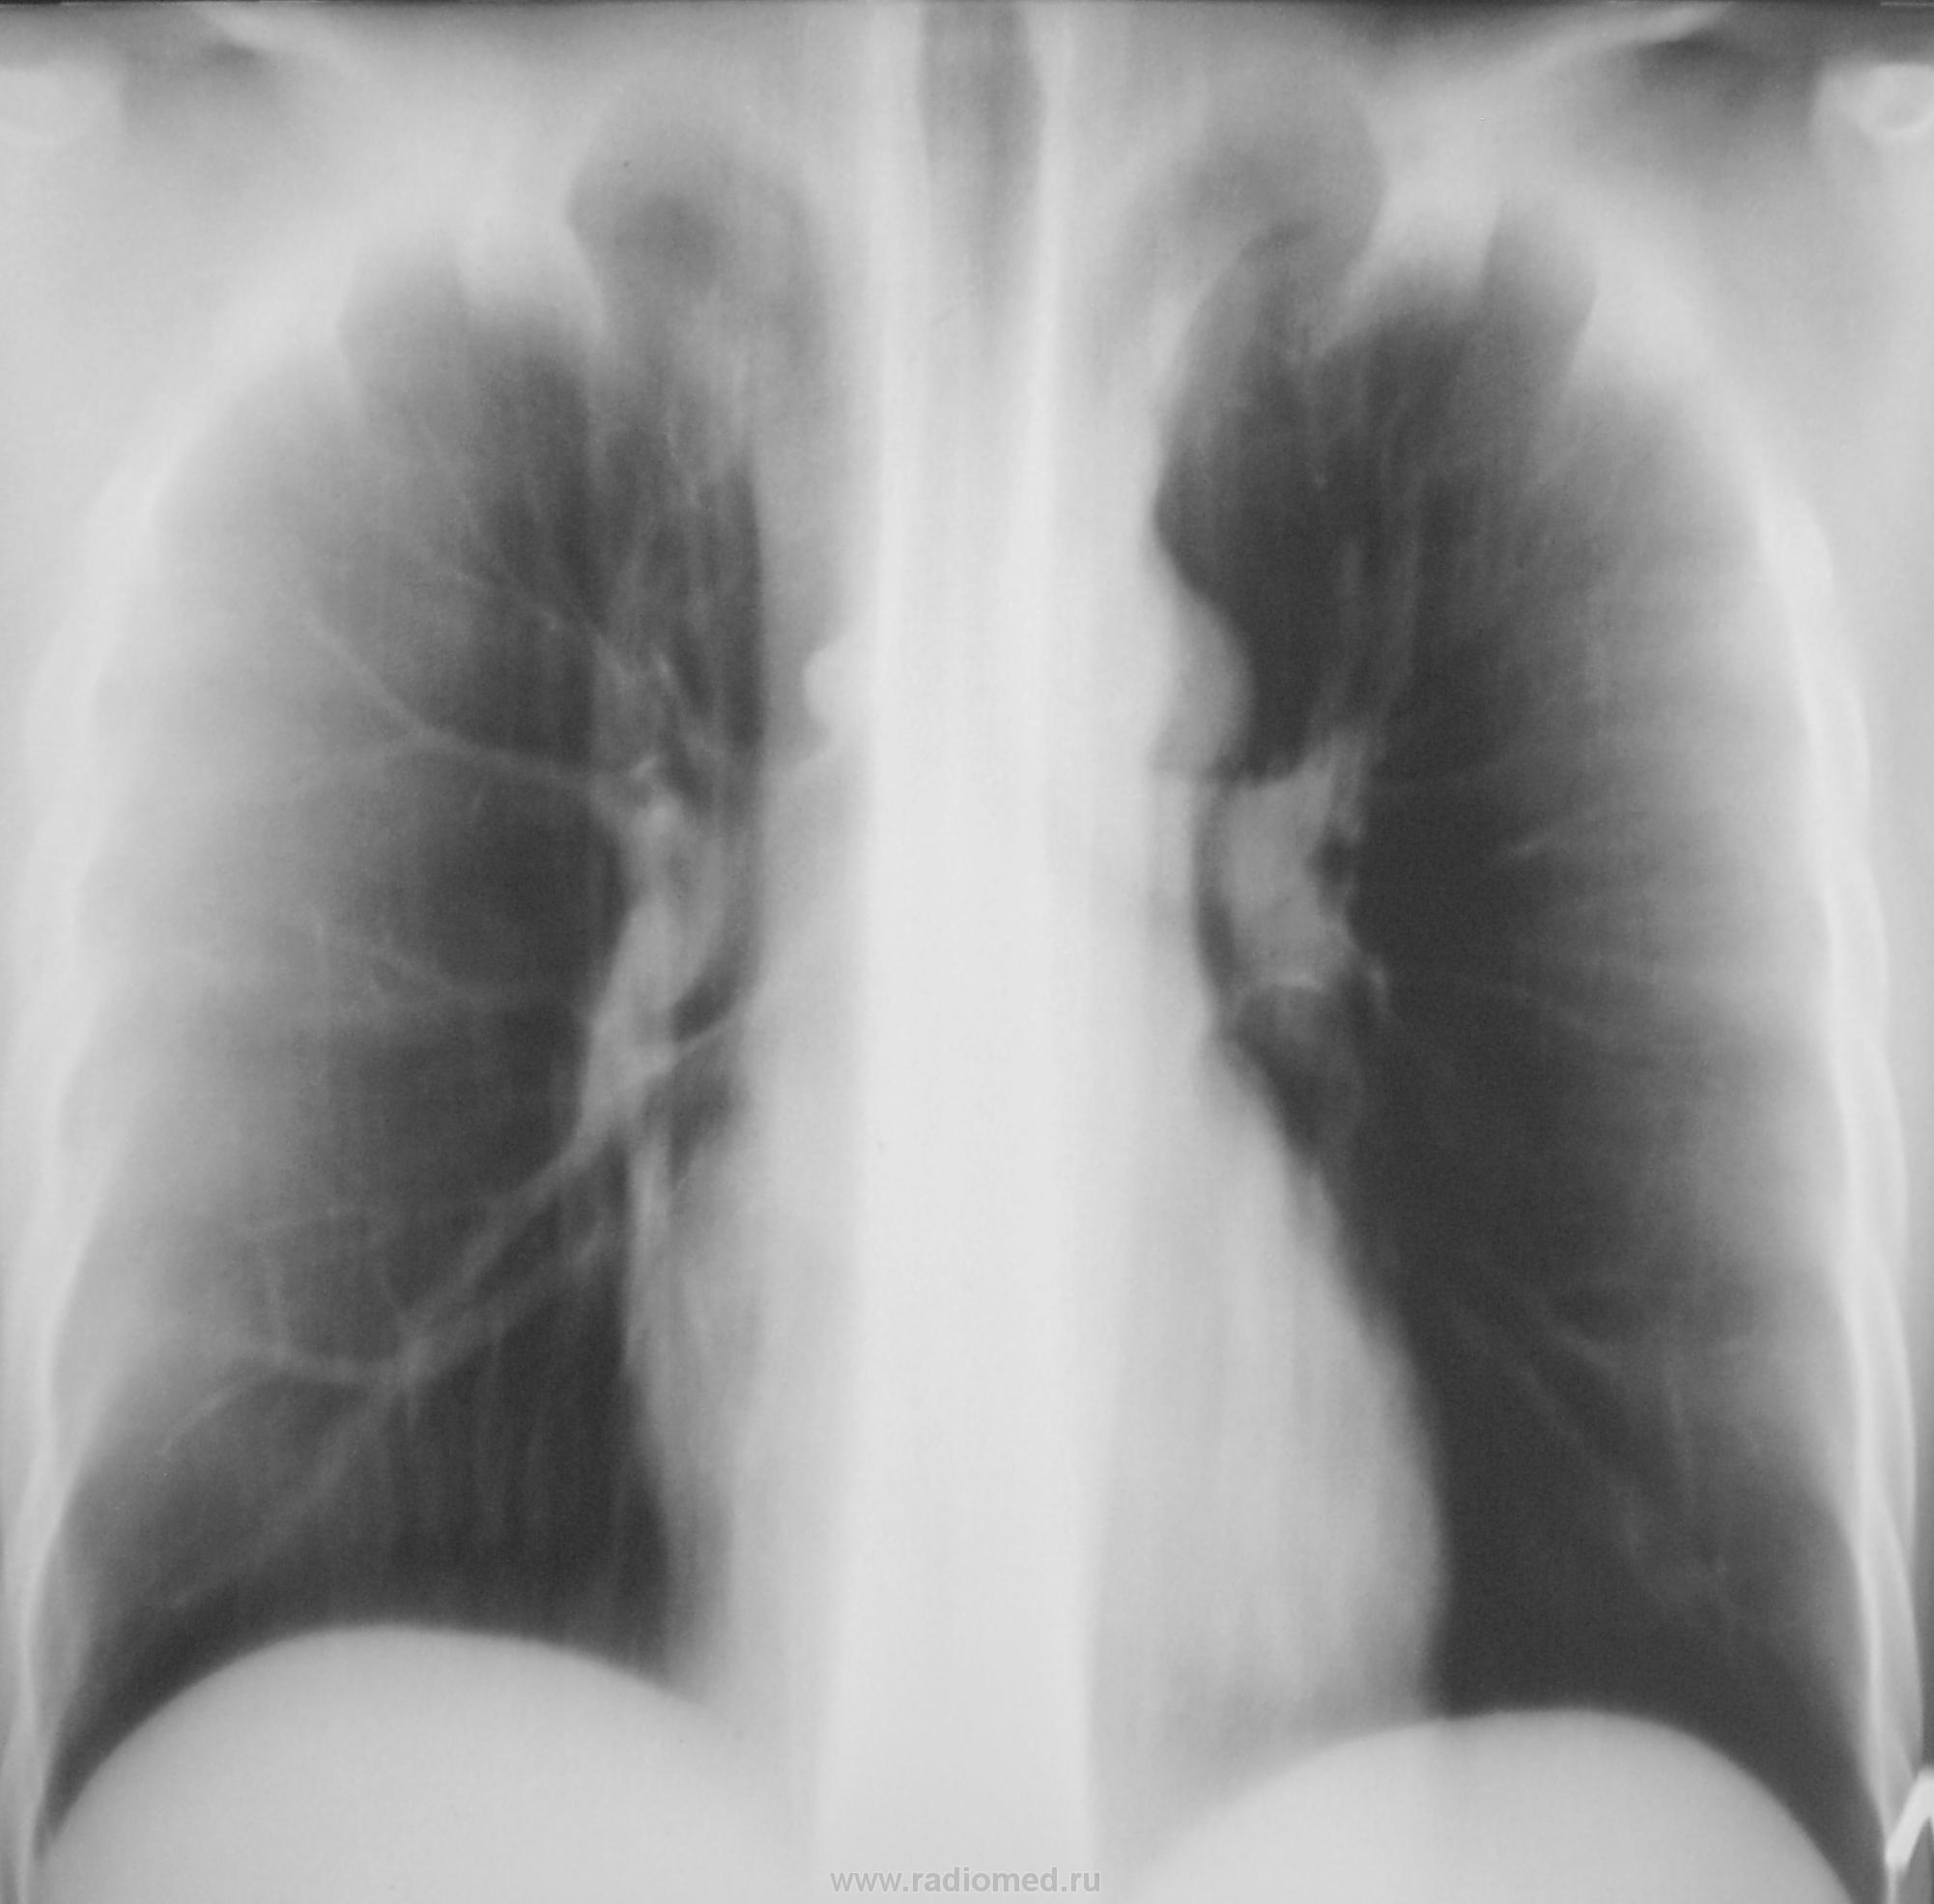

Да, у меня, как правило, "танец" начинается с верхушек.

И, интересует мнение коллег, хотя бы по этому одному срезу.

Органы грудной клетки без патологии.

Смотрите рисунок.  Заключение написано на снимке. Кроме очагов в легких, имеется увеличение паратрахеального лимфатического узла. В ПТД на лечение.  Nikolas